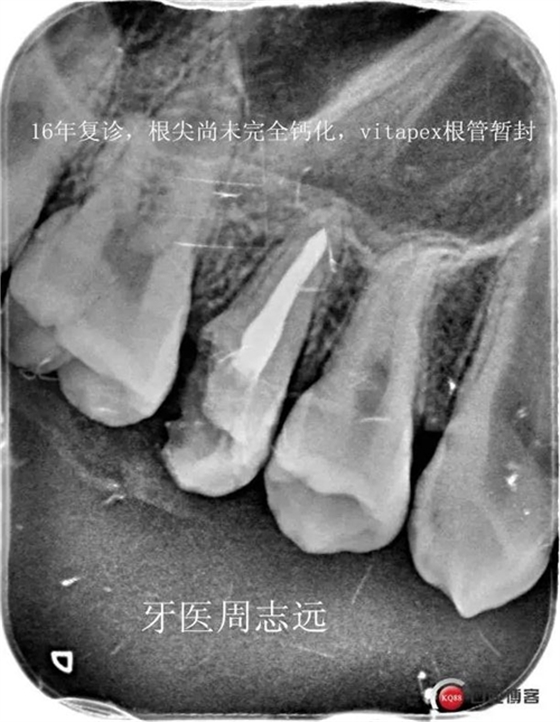

患兒于15年右上恒5牙髓炎就診,檢查發(fā)現(xiàn)根尖孔未閉合,與家長溝通后采取根尖誘導(dǎo)成形術(shù)。RCT完成后vitapex暫封根管,要求半年復(fù)查一次。16年復(fù)查根尖未見明顯異常,但根尖孔未完全閉合,沒有完全鈣化,vitapex再暫封根管繼續(xù)誘導(dǎo)。17年復(fù)查發(fā)現(xiàn),根尖孔完全閉合,X線片顯示形成鈣化屏障,完成根充。由于牙體缺失過多,并且患者后期可能需要進(jìn)行正畸治療,考慮到患者家庭條件因素,選擇進(jìn)行樹脂嵌體修復(fù)。后期等患者建合完成或者達(dá)到矯正時(shí)機(jī)時(shí)再根據(jù)情況選擇修復(fù)方式。告知定期復(fù)查。